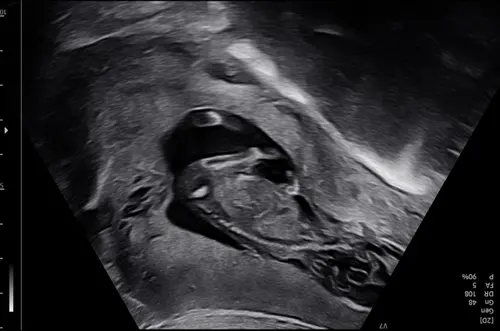

Ik heb deze vanmiddag geplaatst in het andere topic, is met 13+1. Ik heb 1 reactie ontvangen, zijn er nog mensen die een uitspraak kunnen/willen doen op basis van de nub? 🥰

Misschien helpt dit. De echopraktijk voor pretecho’s zegt bij deze echo een meisje omdat de nub vlak loopt aan het einde.